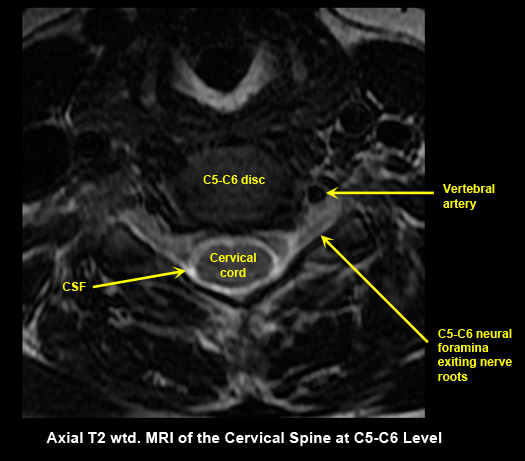

MR Brain and Spine